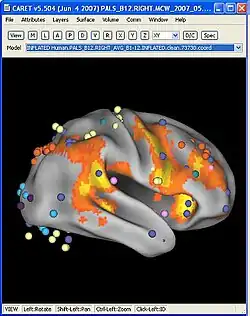

Caret (software)

CARET (Computerized Anatomical Reconstruction Toolkit) is a software application for the structural and functional analysis of the cerebral and cerebellar cortex. CARET is developed in the Van Essen Laboratory in the Department of Anatomy and Neurobiology at the Washington University School of Medicine in St. Louis, Missouri.

CARET's capabilities

- Display of activation foci.

- Mapping of fMRI volumes onto surfaces.

- Visualization of contours, surfaces, and volumes.